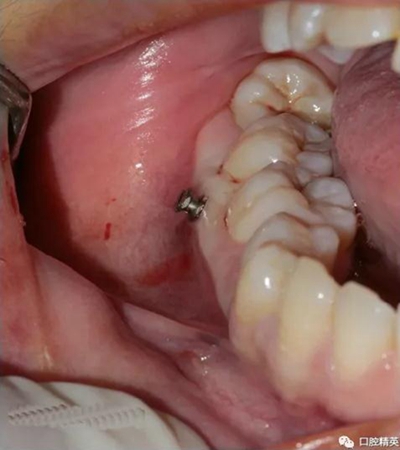

再次,植入微型種植體,在附著牙齦處不需要粘骨膜翻瓣,在牙槽黏膜處則需要切開黏膜以避免植入時(shí)軟組織被卷入,植入部位通常在膜齦結(jié)合部位或偏根方2~3mm,植入角度與骨面垂直并傾斜15~20度,即向根尖方向植入,術(shù)后拍根尖片以確認(rèn)與牙根的關(guān)系。術(shù)后口服抗生素預(yù)防感染并進(jìn)行口腔衛(wèi)生宣教。

上頜種植釘?shù)闹睆?.6,長度11mm;下頜直徑2.0,長度9mm

1、上頜種植釘常見位置在5,6之間;下頜種植釘常見位置在6,7之間。

5 、常見失敗原因:感染;旋轉(zhuǎn)螺絲刀幅度過大;排斥反應(yīng);軟組織夾入;骨質(zhì)疏松;使用時(shí)力值過大。

6 、常見術(shù)中和術(shù)后并發(fā)癥:損傷牙根或牙周膜;種植釘斷裂;感染;種植釘松動(dòng)(松動(dòng)率:約10%,下頜大于上頜)